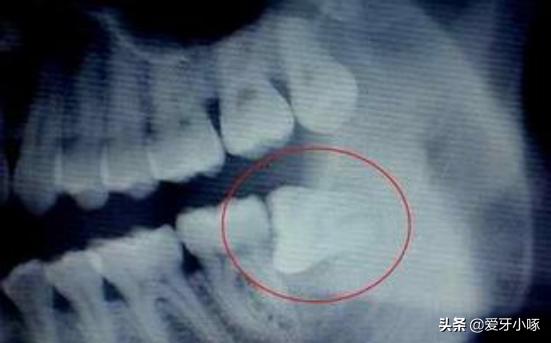

前倾的阻生智齿

这样的智齿不到会顶到第二磨牙,还会影响整个牙齿的排列情况。也会严重影响我们的咀嚼功能!